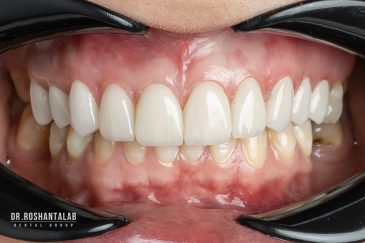

طراحی لبخند هالیوودی با متدهای لمینت سرامیکی دندان و کامپوزیت ونیر در کنار اصلاح فرم، خدمات بلیچینگ و روکش دندان، زیبایی چهره شما را تکمیل میکند.ترمیم دندان

انتخاب بهترین متخصص ایمپلنت که به تکنیکهای روز دنیا مسلط باشد، تضمینکننده سلامت فک و زیبایی لبخند شماست. در کلینیک دندانپزشکی دکتر روشنطلب، ما با بهرهگیری از تجهیزات دیجیتال در ۵ شعبه فعال (تهران، اصفهان، رشت و استانبول ترکیه)، خدمات تخصصی کاشت ایمپلنت دندان را برای بیمارانی که کیفیت و دقت برایشان اولویت دارد، ارائه میدهیم. در این متد، پروسه درمان با ظرافت بالا انجام شده؛ راهکاری ایدهآل برای کسانی که به دنبال درمان بدون درد با بالاترین نرخ موفقیت هستند.